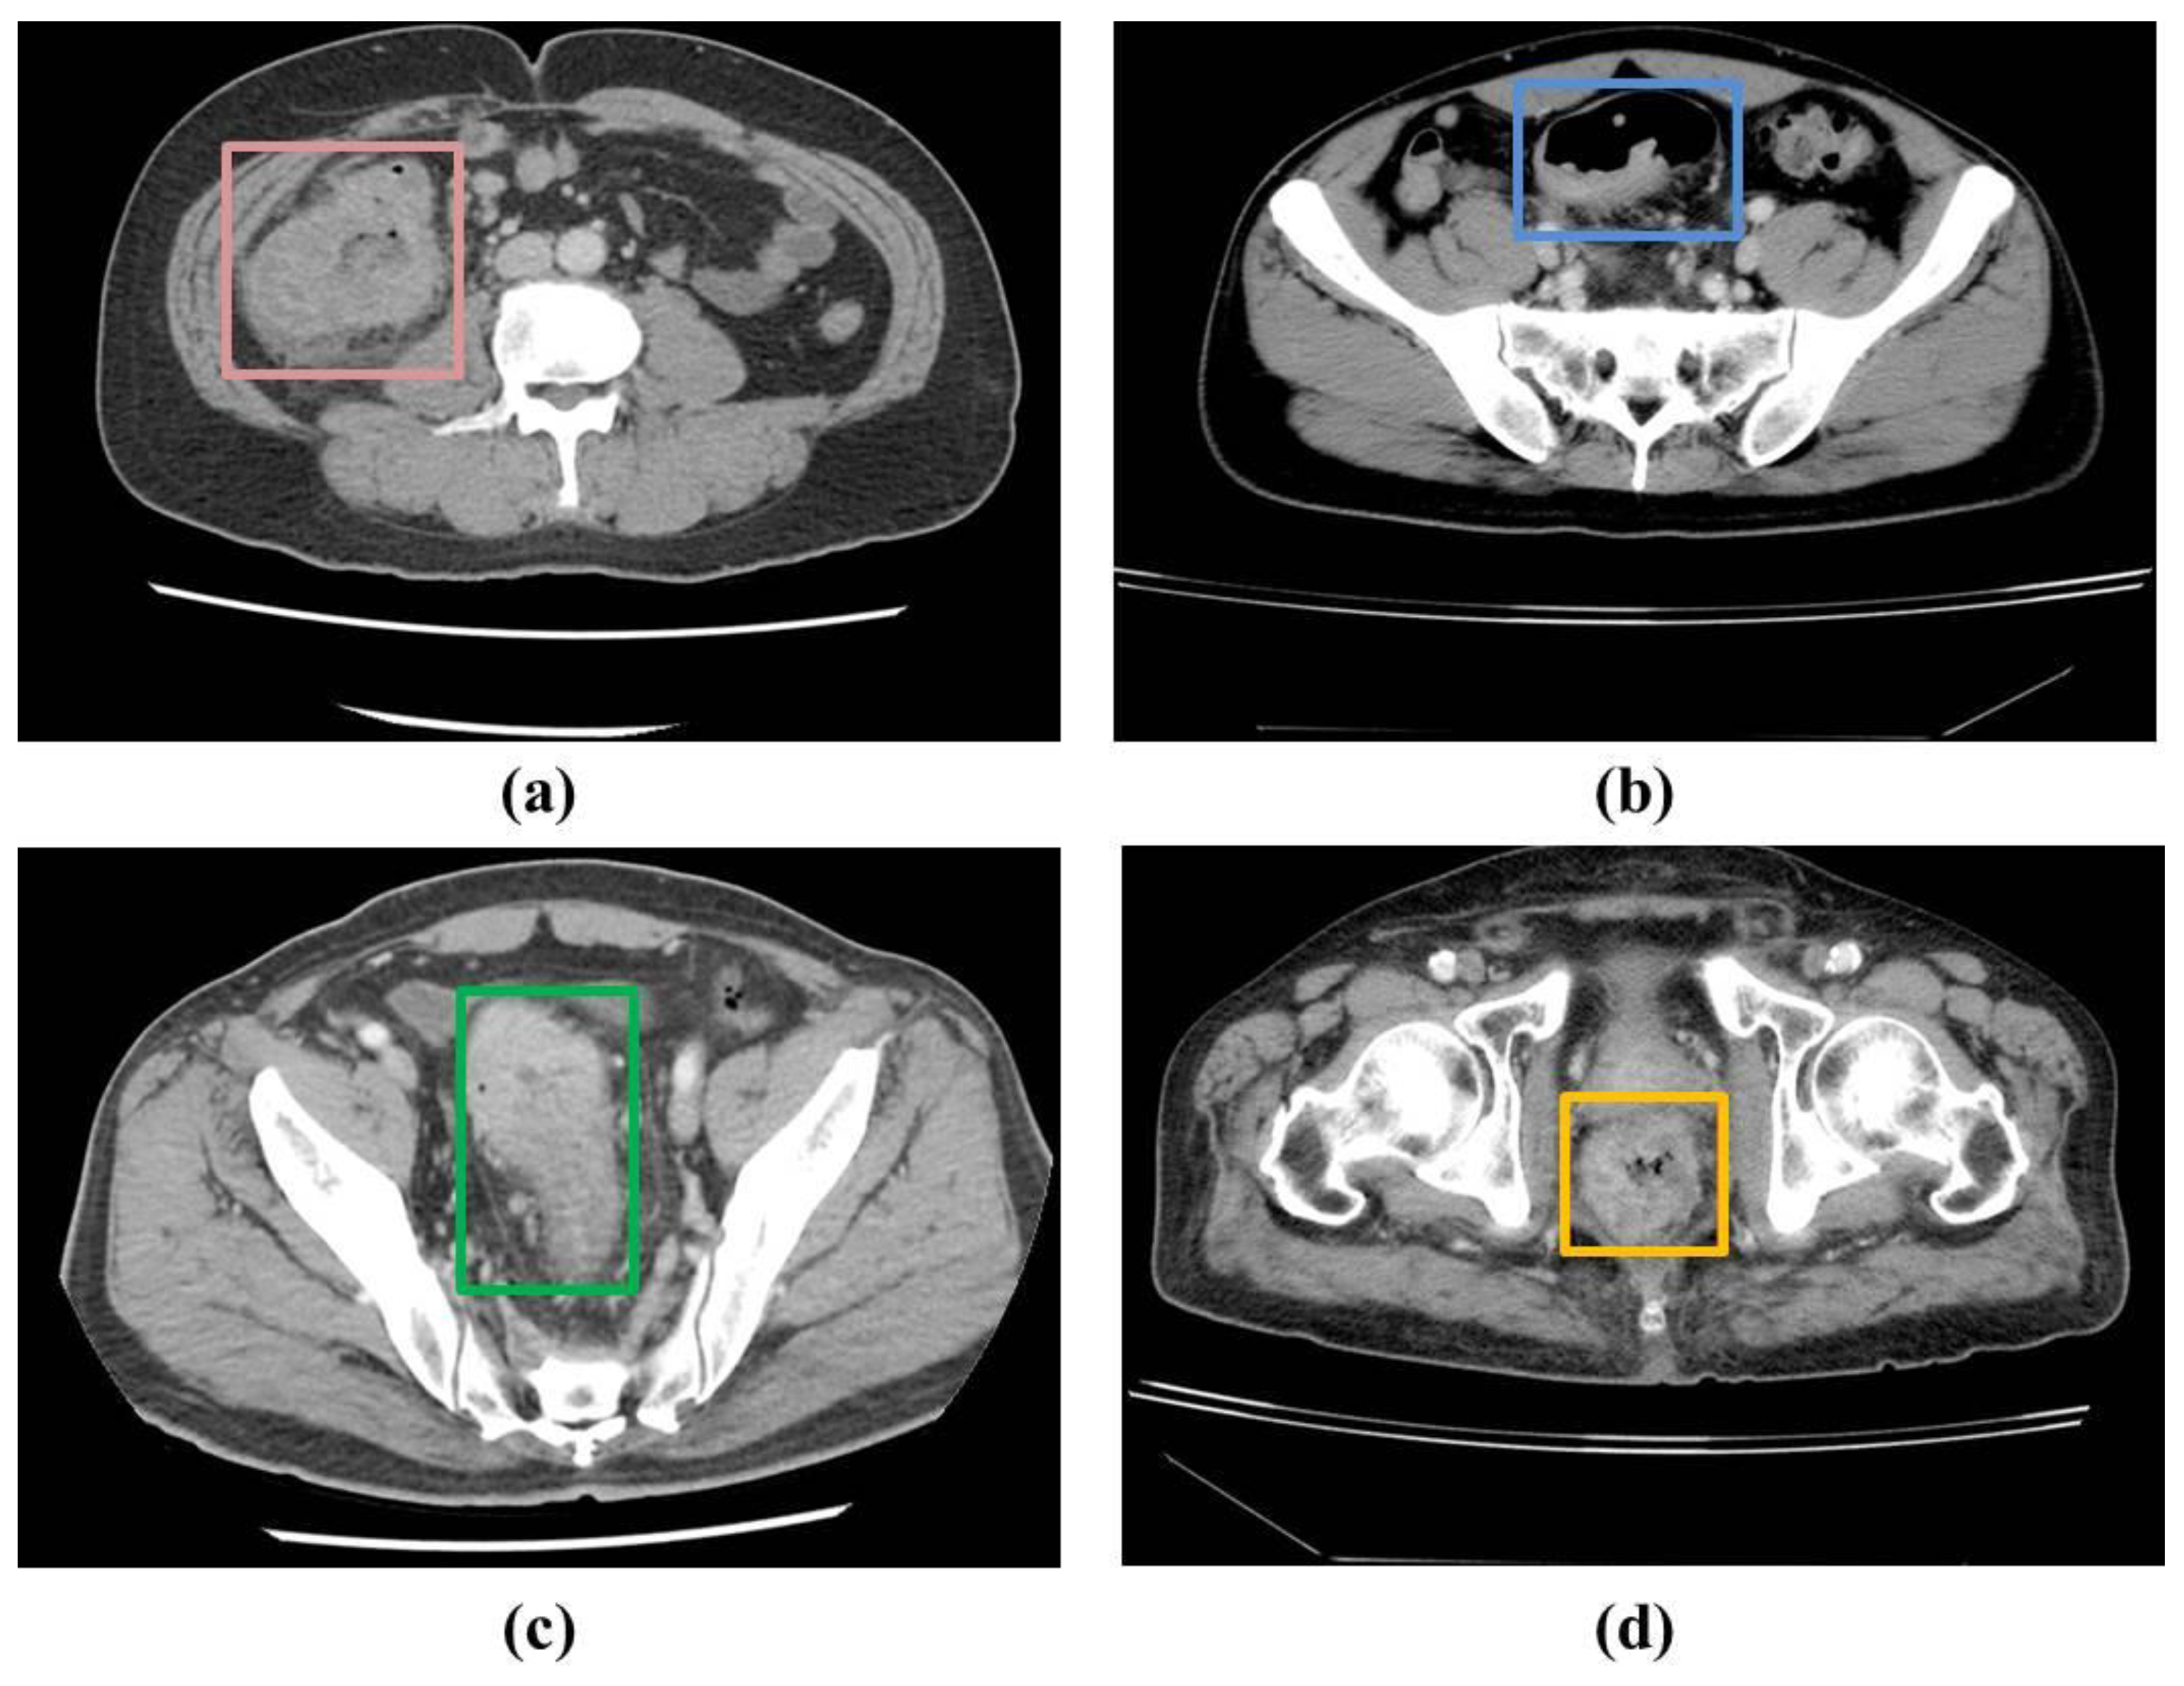

In the patients’ CT scans, the tumors were observed to be localized either in the colon or rectal regions. Irrespective of the location of the CRC, it was necessary to annotate the CRC region for training the deep learning-based detection model in a supervised manner. As a result, two radiologists with approximately 5 years of experience annotated the CRC region in the raw CCT slices using OSIRIX MD v10.0.5 (Pixmeo SARL, Bernex, Switzerland) [20] and Horos (https://horosproject.org/) (version 3.3.6) (accessed on 20 June 2021). Figure 1 shows examples of the ground truths. A total of 1558 slices were annotated out of 16184 slices in the 190 patients used for the model derivation.

Figure 1. Examples of the ground truths provided by the experts: (a,b) colon region, and (c,d) rectum region.